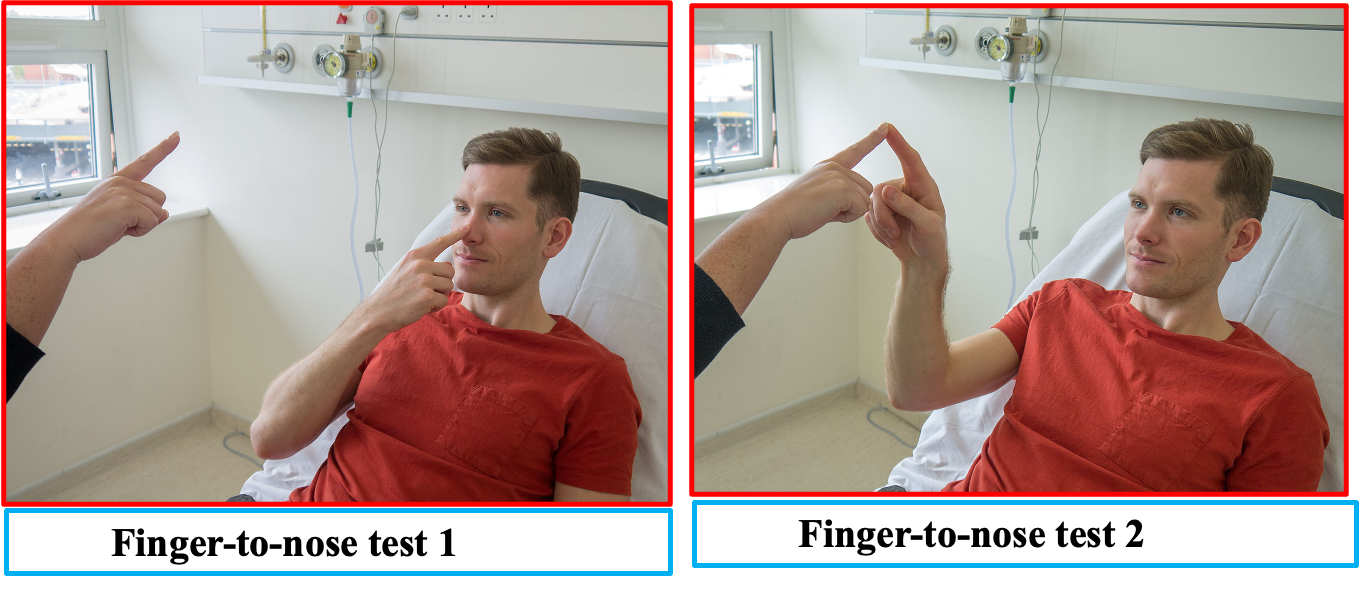

C) Fingers-nose

Finger-to-nose with moving target

Stationary finger-to-nose with eyes closed

FINGER NOSE TEST